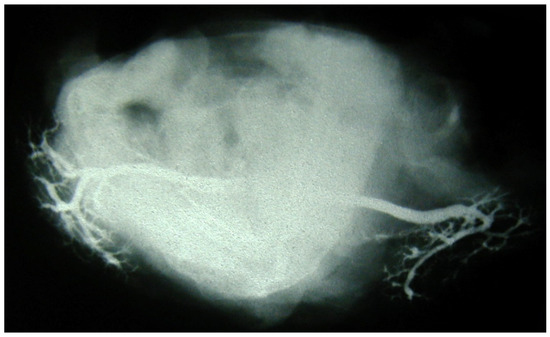

Immediately after injection, the specimens underwent image acquisition on standard radiographic equipment. Their positions in the frontal and the axial planes were controlled beforehand and verified via fluoroscopy (Figure 1 and Figure 2). A metal reference lamina of known width was placed in the vicinity of the specimen, for the purpose of the calibration of dimension, i.e., resolving the magnifying influence of distance between the X-ray tube and the specimen (film). Sialograms were taken under the following parameters: a generator of 42–50 kV and exposure of 3.2–5.0 mAs.

Figure 2. Postmortem sialography of submandibular glands, axial plane. The genu of Wharton’s duct is clearly visible.